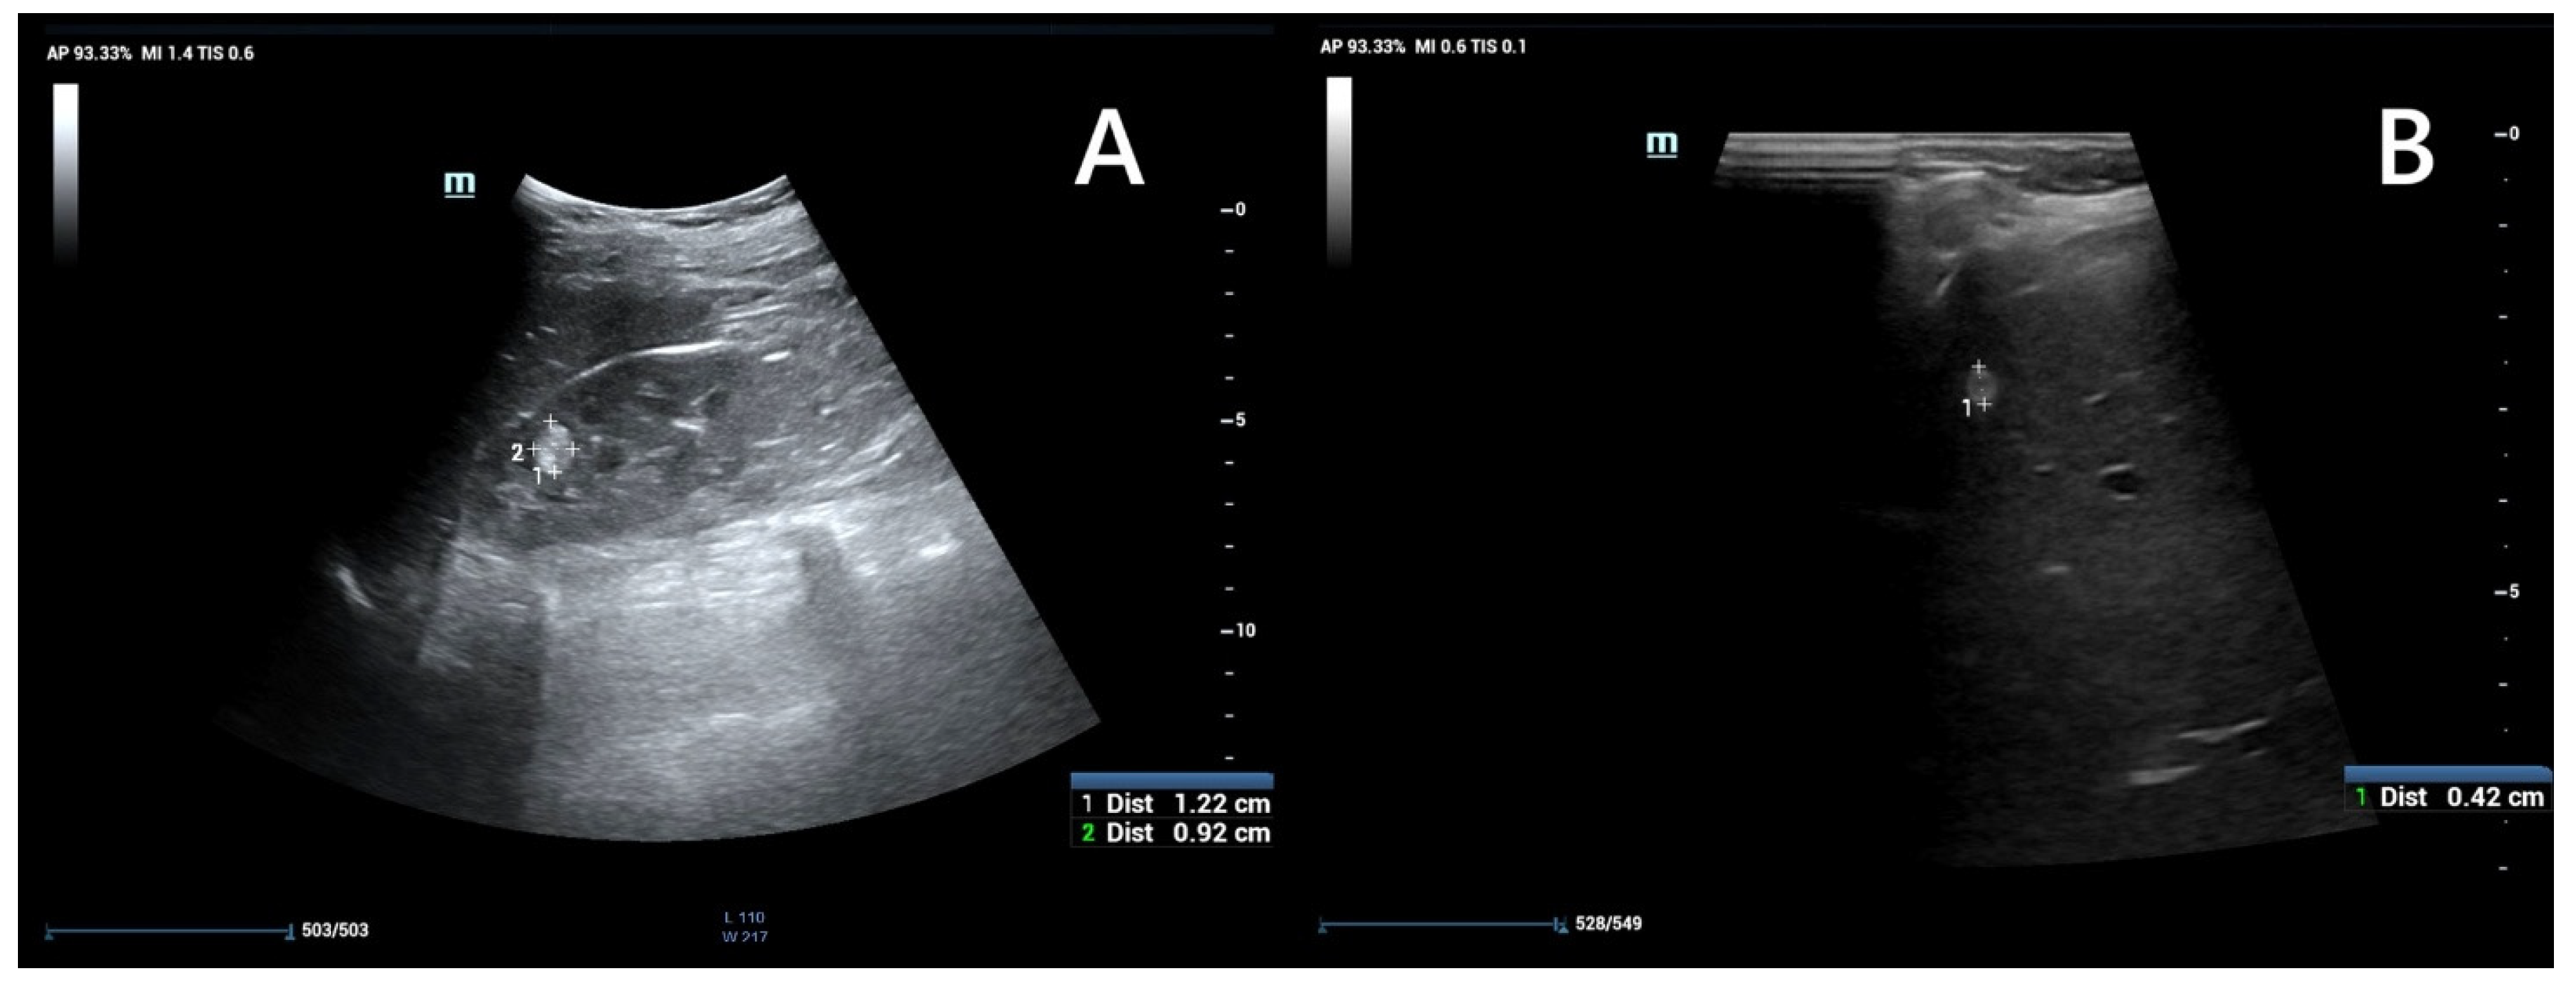

5.1. Renal Ultrasonography

Ultrasound is widely recommended as a first diagnostic approach, helpful in detecting and monitoring lesions within kidney and other accessible parenchymal organs (Figure 4), and differentiating between their solid or cystic structure. When performed by an experienced operator, it is often sufficient for evaluating simple cysts; however in patients with large body mass, thick cystic septa, or not entirely anechoic lesion contents, further assessment with CT or MRI is recommended [44,47]. The kidney should be carefully scanned in both coronal and axial planes to ensure visualization of areas potentially obscured by artifacts, such as colonic gas or rib shadows [47].

AMLs in ultrasound typically appear as hyperechoic to renal parenchyma, homogeneous lesions, but their appearance can vary depending on the relative composition of fat, muscle, and vascular tissue [48]. The imaging appearance is non-specific, as up to 8% of renal cell carcinomas (RCCs) can also be hyperechoic, and confirmation by CT or MRI is recommended. However, it can provide valuable indicators: if the tumor is less than 3 cm and an acoustic shadow is present, angiomyolipoma is the most likely diagnosis. In contrast, the presence of a hypoechoic halo and intratumoral cysts suggests clear cell renal carcinoma (CCRC) [44,47,48]. Atypical or fat-poor AMLs require diagnostic evaluation with other, more advanced imaging modalities, as ultrasound images are varied and non-specific [48].

Figure 4. An ultrasound of a 13-year-old boy. Kidney with focal lesions with features suggestive of AMLs (A). Multiple oval hyperechoic lesions within the liver—most likely AMLs (B).